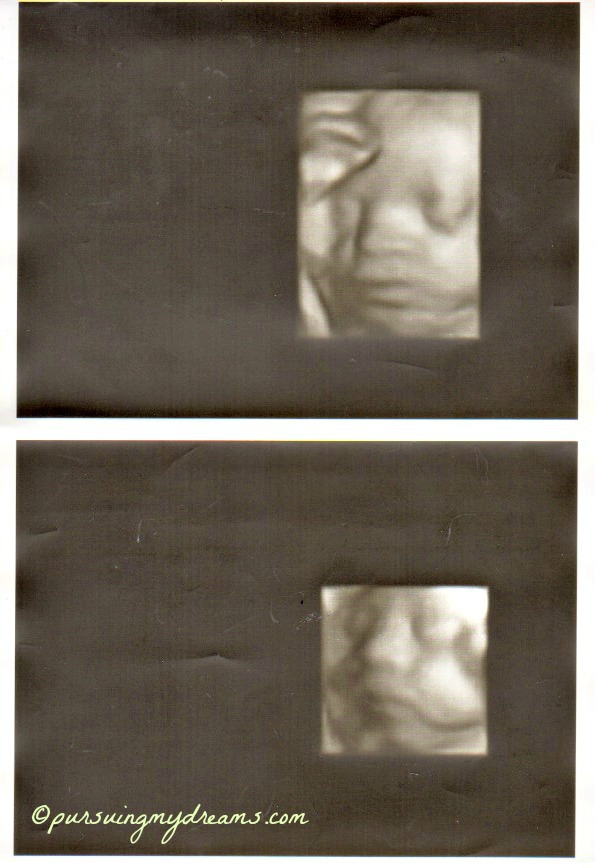

Sebagai penutup saya sertakan foto hasil usg anakku. Ini usg saat usia kehamilan 25 minggu. Dilakukan di kliknik Mannheim. Setelah itu sampai saat ini dokter tidak pernah melakukan pemeriksaan usg lagi karena semuanya baik-baik saja. Jadi hanya diperiksa posisi kandungan.

Iya bang keliatan jelas, padahal itu masih 25 minggu. Ga tau saya usg apa namanya hehehe.

Hidung anakku ngikut aku Ndang alias pesek, dokternya bilang gitu 😆 .

wah… udah kelihatan jelas. itu pake uSG 3 dimensi yah? mirip sama buku ….. ah lupa judulnya… isinya seh kebanyakan foto perkembangan janin di setiap minggunya